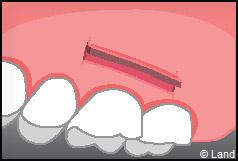

LES TECHNIQUES AVEC APPORT DE GENCIVE OU « GREFFE DE GENCIVE » :

Elles font appel à un prélèvement sur le patient à un endroit où elle est en excès, qui est ensuite posé sur la récession.

Les greffes épithélio-conjonctives :

Elles sont pratiquées pour des zones non esthétiques de la cavité buccale, à cause de l’aspect « rustine» que la cicatrisation leur confère.